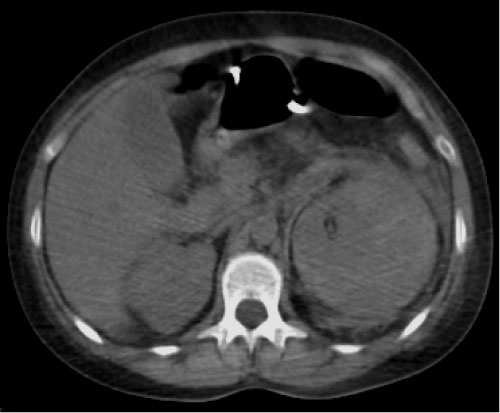

A 37-years-old single woman who presented to emergency department with loss of strength in the right superior limb for three months and associated with loss of sensitivity on feet and legs. She was admitted to the hospital for investigation. In her physical examination was pallor, tachycardia, loss of strength in the right arm and loss of the pain sensitivity in legs and feet. Blood pressure: 140 × 100 mmHg. Evolved with diffuse abdominal pain. Lab results: hemoglobin = 6 (admission); hemoglobin = 3 (before being referred to the computed tomography), hematocrit = 28%, leukocytes = 21.610, neutrophil segmented = 59%, eosinophils = 10%, platelets = 898.000, erythrocyte sedimentation rate = 105, creatine phosphokinase = 3.396, C-reactive protein > 100, urea, creatinine and urinalysis without abnormalities. After all medical conducts the patient do not resist. The computed tomography showed following images (Figure 1, Figure 2 and Figure 3).

Figure 1: Non-contrast phase. Inflammatory stranding in the left retroperitoneal space. Kidney showing loss contour. View Figure 1